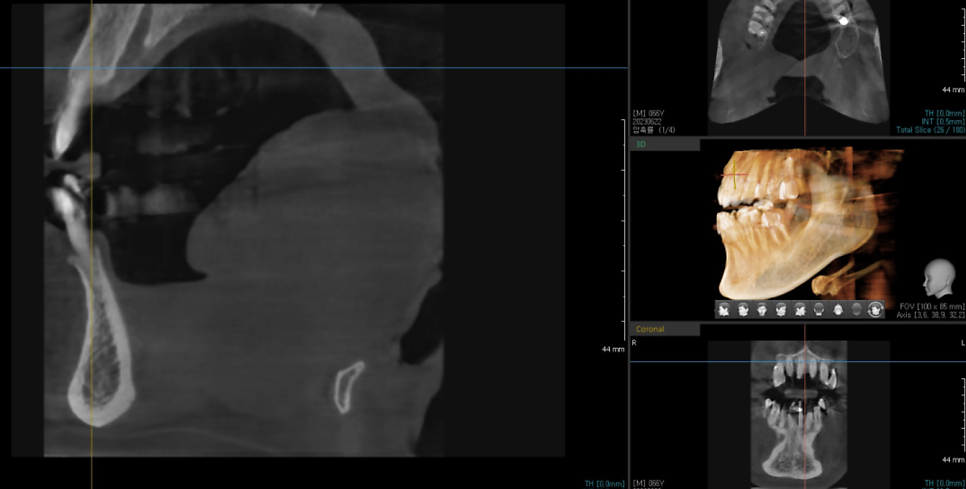

ct를 찍어 분석해보았습니다.

턱 뼈 상태는 아주 굿이었는데요.

뼈 이식을 안하고 그냥 심어도 되는 상태였습니다.